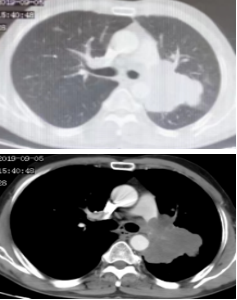

影像学-增强CT检查:左肺见不规则软组织影,包绕肺门结构,病变轴位长径约7.5cm,左肺散在结节影,最大约4.5cm;纵隔、肺门见多发淋巴结肿大,纵隔7组短径约2.0cm。

CT检查——基线

影像学-增强CT检查:治疗2周期后,左肺病灶明显缩小达52.9%,疗效评估为PR。

CT检查——治疗2周期后

治疗6周期后,左肺病灶明显缩小达58.6%,疗效评估为PR。

CT检查——治疗6周期后